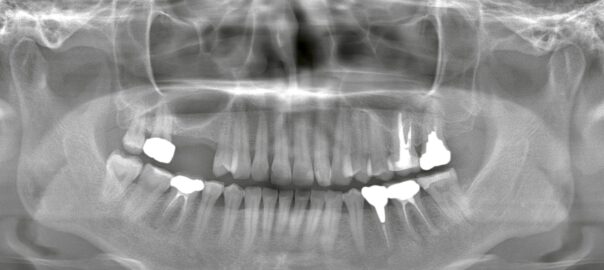

- 2026/01/30 ブリッジが外れる・痛い…インプラントへ変更した症例

こんにちは、静岡市駿河区石田の小嶋デンタルクリニックです。 これまで欠損部にブリッジ治療を行っていたものの、 ・ブリッジが外れる ・噛むと痛みが出る といった症状を繰り返すため、ご相談に来院された患者様です。 ブリッジ治 … 続きを読む ブリッジが外れる・痛い…インプラントへ変更した症例